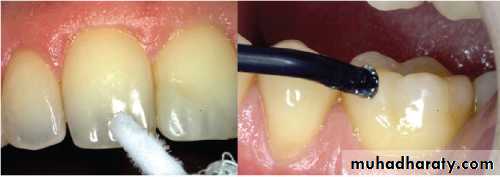

Cold TestIsolating the quadrant with the tooth to be tested.

1- Cold water

2 -cold air from a 3-way syringe directed against the crown of 3-previously dried tooth.

4- Use of ethyl chloride spray.

5- Ice Stick

6- CO2 snow

Correct placement